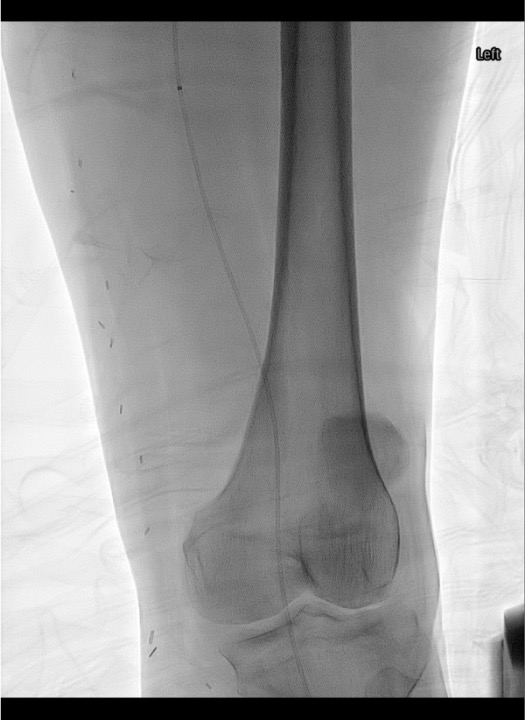

Angiographic Assessment & Endpoints

- Runoff angiography through sheath: 4 mL/s × 8 mL for outflow vessels; increase to 16–20 mL for lower leg and foot imaging

- Document baseline outflow to foot before initiating any intervention

- After crossing occlusion, gentle test injection to confirm intraluminal position and distal flow

- Select infusion catheter (Unifuse) to span entire lesion length; available in 10 cm increments (10–50 cm)

- Angiographic endpoints: restoration of inline flow, resolution of filling defects, treatment of underlying lesion

- If >50 cm occlusion, position 50 cm catheter with proximal marker at proximal extent; lytic medication flows distally as flow re-establishes